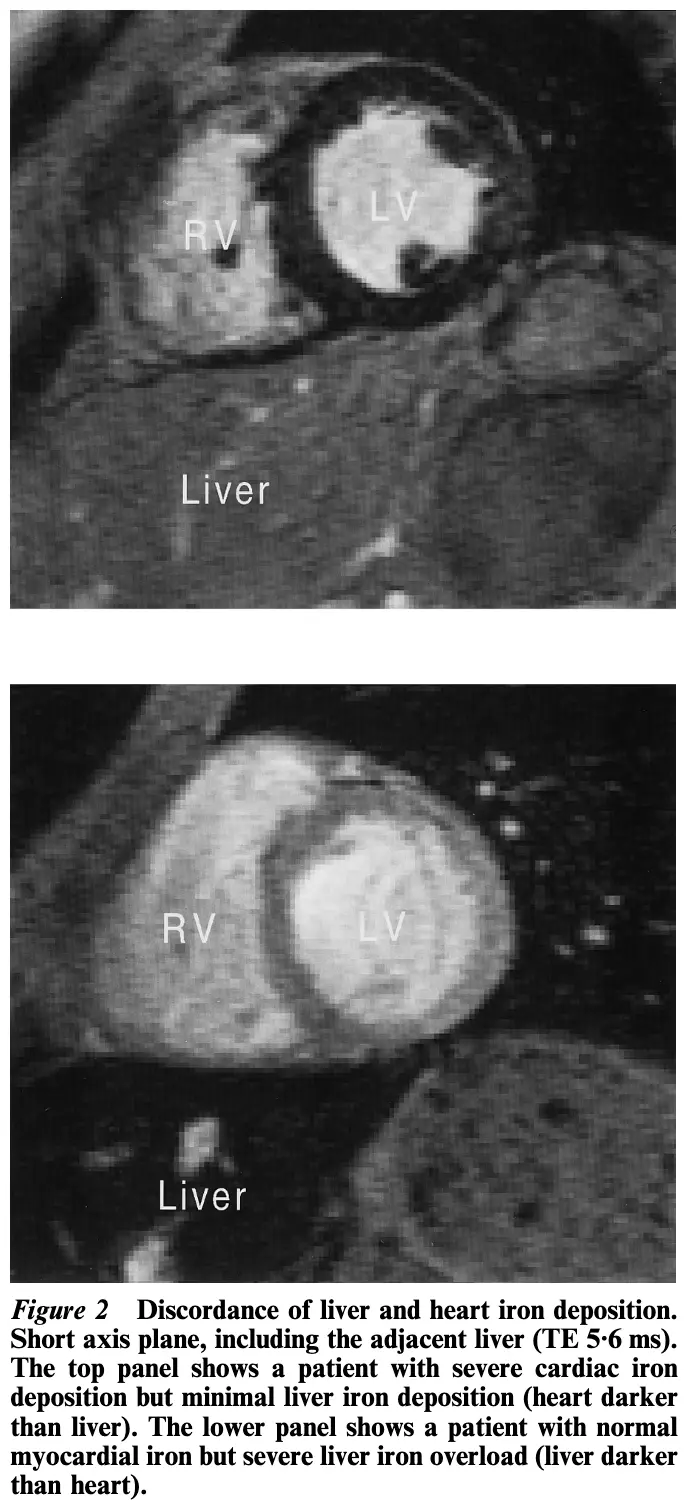

• Quantify iron in the heart 🫀 and the liver

• Heart 🫀 (trace within the septum): <20 is concerning for iron overload

• Liver: <10 is concerning for iron overload